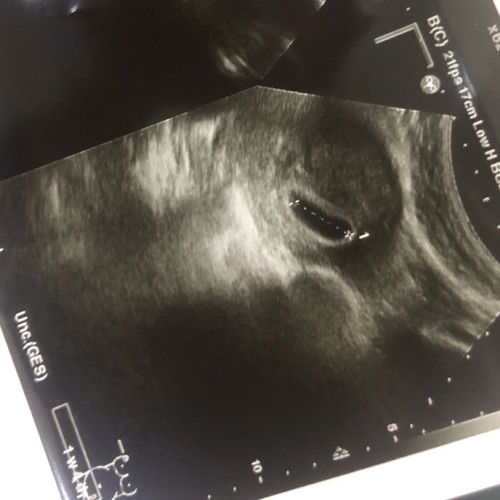

Hai bunda, mau cerita sedikit dan sekalian minta saran. Dikehamilan ke2 ini aku bingung prihal HPL si adek karna waktu hamil kontrol di 3 tempat karna kurang cocok dg dokternya. Awal usg Dr.obgyn pertama di fotonya hpl juli, kemudian di faskes 1 dan Dr.obgyn yg sekarang hpl juni cuma beda tgl aja. Kira” mana yg benar ya bun? #bantujawab #ingintahu